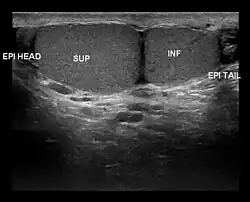

| Ultrasound scan showing a side view of Type A3 polyorchidism, with annotations showing the superior and inferior testes and the head and tail of the epididymis |

- Type A3: The supernumerary testicle shares the epididymis and the vas deferens of the other testicles.

Type A3 is the most common form of polyorchidism, and types A2 and A3 together account for more than 90% of cases.[3] In 65% of cases, the supernumerary testicle is found in the left scrotal sac.[1]